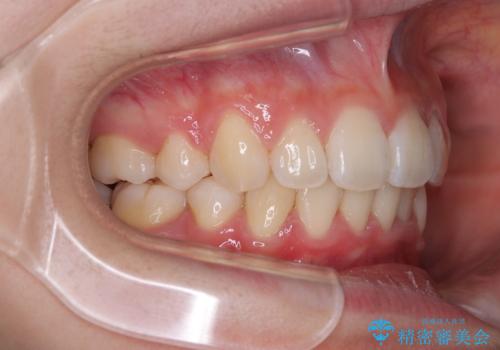

- 前に傾斜して飛び出した上顎前歯を気にして来院された患者様です。

上下前歯の前後差が大きく、下顎前歯が隠れるほど深い咬合で、咬合力が強い状態でした。

深い咬み合わせの改善に時間がかかりましたが、下顎前歯がしっかりと見えるまでに整えることができ、口元の突出感も大幅に改善することができました。